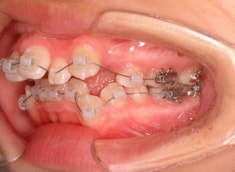

治療開始時

治療開始から5ヶ月後